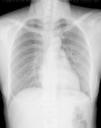

Saturation was maintained at approximately 99% with the oxygen cannula at 2L/min. Physical examination showed palpable subcutaneous emphysema involving the submandibular region, anterior and lateral aspect of the neck, as well as the bilateral supraclavicular regions. There were minor inflammatory signs but there was no local dental infection. Chest radiograph showed pneumomediastinum and subcutaneous emphysema in the neck region (Fig. 1). A computed tomography scan was performed that showed: emphysema extending from the mandibular region to the mediastinum (Fig. 2A and B), as well as the presence of pneumopericardium and left side pneumothorax (Fig. 3A and B) The laboratory tests showed slightly elevated white counts 12400/μL without shift-to-left. The band form was 4% and the segmented form was 80% of total leukocytes. C-reactive protein was 7.4mg/dL. After treatment with a second-generation cephalosporin administered intravenously along with oxygen and oral non-steroid anti-inflammatory drug, the fever subsided within 24h after admission and the symptoms resolved. The patient was discharged 4 days later. After discharge, the patient took oral first-generation cephalosporin for an additional five days. She had a complete clinical and radiological recovery without recurrence of disease (Fig. 4).